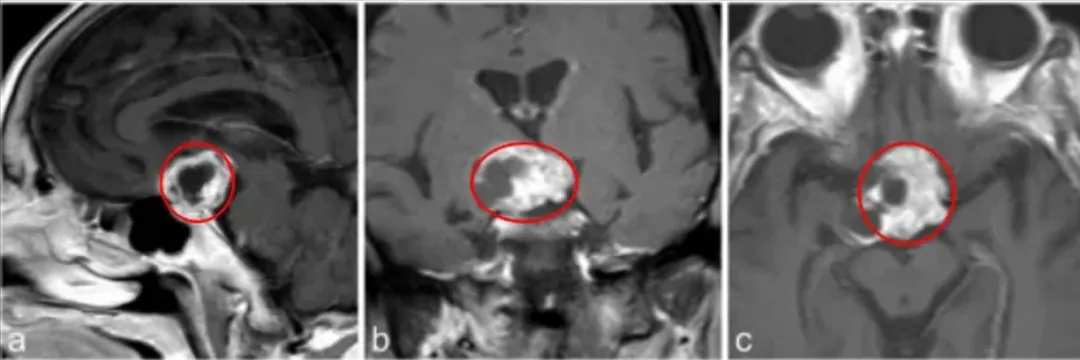

术前MRI:不对称的鞍上强化病变,怀疑颅咽管瘤。

a–c图中,MR成像显示鞍上部分实性,部分囊性对比增强病变,高度可疑的颅咽管瘤。